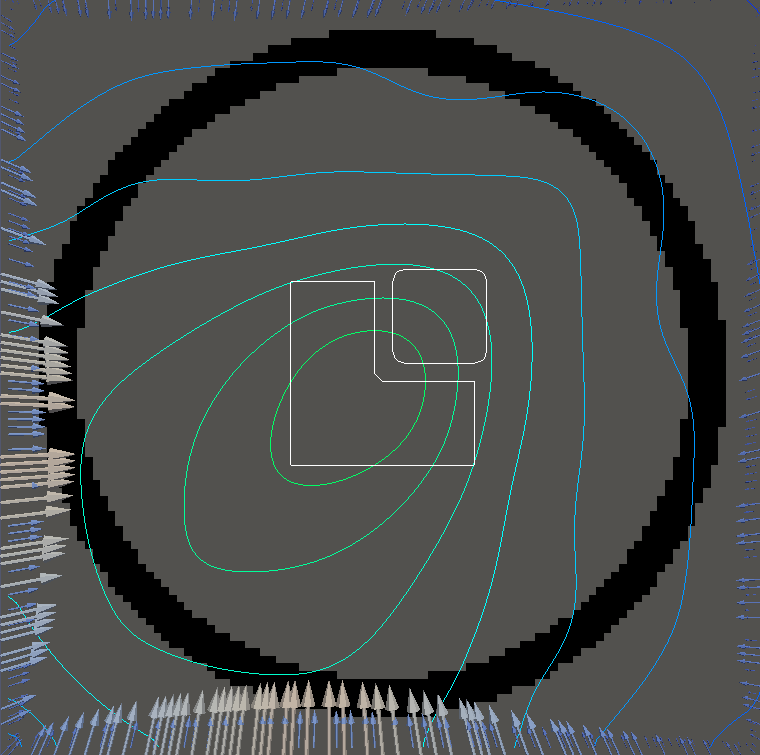

For testing, we use three tumor/risk region regions similar to those in [13]. Specifically, we define the regions in Table 3 and are shown in Figure 1; the void region is shown in black and the tumor and risk regions are traced in white. In the basic target case, seen in Figure 1(a), the tumor region is a box, as is the risk region. The second, intermediate target case, seen in Figure 1(b), involves an L-shaped tumor around a box-shaped risk region. Finally, the complex target case in Figure 1(c) involves a C-shaped tumor around a risk region.

Figure 2 shows the optimal boundary source term for both and The vectors shown on the boundary are the time-integrated values of normalized and then scaled by In Figures 2(a), 2(c), and 2(e) (corresponding to ), the isolines are spaced at intervals of the maximum of the desired dose (here, 5). In the intermediate and tracking cases, we see that relatively low dose levels are attained, primarily due to the high penalty to any dose deposited in the risk region. In Figures 2(b), 2(d), and 2(f)(corresponding to ), the isolines are spaced at intervals of of cells killed. Here a high proportion of the tumor cells are killed (in each case ) while in the Intermediate and Basic cases, the tumor has at least survival; in the Complex case, the risk region has survival.

The dose deposited in changes significantly when we alter the relative weights and . In Figure LABEL:fig:optlowrisk, we see the results for solving and where we set and (all other parameters are unchanged). In both the basic and intermediate cases, the dose delivered to the tumor is significantly higher while also remaining largely concentrated on the tumor. This is slightly less true in the complex case. In the figures for there is no general change in the pattern of cell death, however the risk region in the first two cases has cell survival whereas the complex case has approximately cell survival. However, this lack of change in pattern can partially be attributed to the tumor cells being more susceptible to the radiation dose.